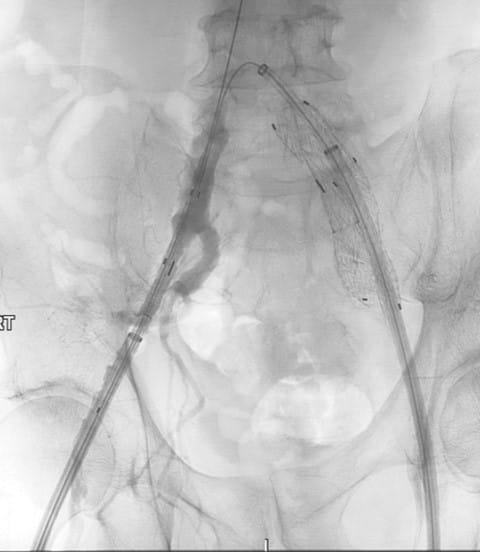

A 76-year-old male presented to UPMC for evaluation of aortoiliac aneurysm disease. His past medical history is also significant for mild emphysema, hyperlipidemia, lung and prostate cancer, and he has no family history of aneurysmal disease or connective tissue disorder. He is without symptoms of cardiac ischemia or peripheral claudication. His preoperative CT scan demonstrated the presence of a small infrarenal abdominal aortic aneurysm measuring 4.8cm, and bilateral large common iliac artery aneurysms, measuring 4cm and 3.8cm on the right and left, respectively. The internal iliac arteries were patent bilaterally (Figure 1 and 2). He underwent endovascular repair of his abdominal aortic aneurysm with placement of bilateral iliac branch endoprostheses (Gore Medical, Flagstaff AZ) for his bilateral common iliac artery aneurysms via percutaneous bilateral common femoral artery access (Figures 3-6). The patient tolerated the procedure well and was discharged on post-operative day two.

Figure 5: Positioning of the right iliac branch endoprosthesis. The up-and-over wire and the main body wire are free of wire wrap. The left iliac branch endoprosthesis is fully deployed.